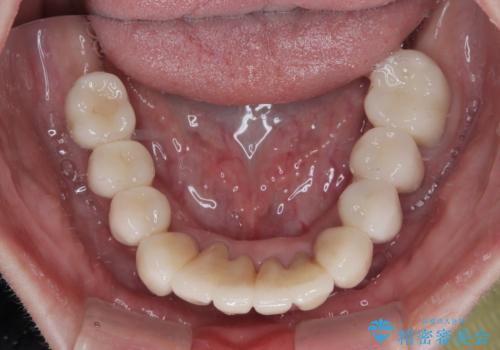

上顎口蓋からの堅い歯肉を移植する角化歯肉移植術を行いたかったのですが、体調不良から実施しなかったため、最終補綴物であるオールセラミッククラウンを装着した後に、知覚過敏や境目が見てしまうといった問題が一部で発生いたしました。

最終的には痛みや違和感のない状態にて治療を終えることができました。